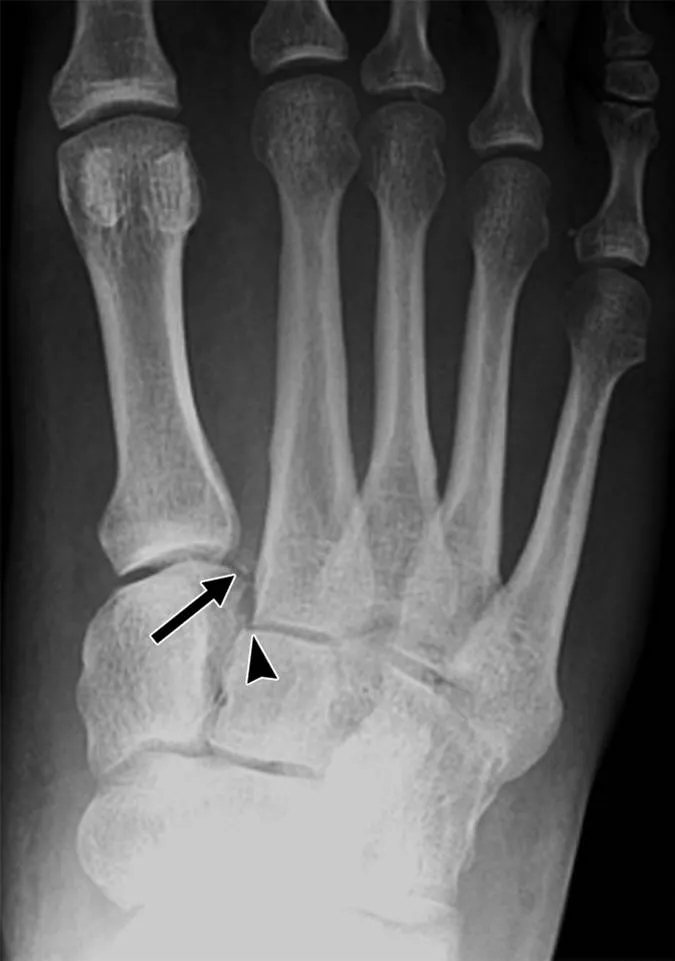

严格说骨裂属于骨折中的一种,不过它和骨折还是有明显的区别。与骨裂最接近的疾病是裂纹骨折,是一种闭合、稳定、不完全性骨折。

而骨裂则是一种不完全性骨折,由于骨关节的连续性和完整性也同样遭到了破坏,因此骨裂属于骨折的其中一种。